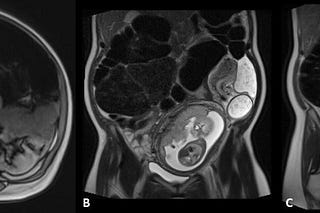

Cecal Volvulus

Jacob C Davis, DO

Apr 5, 2025

2